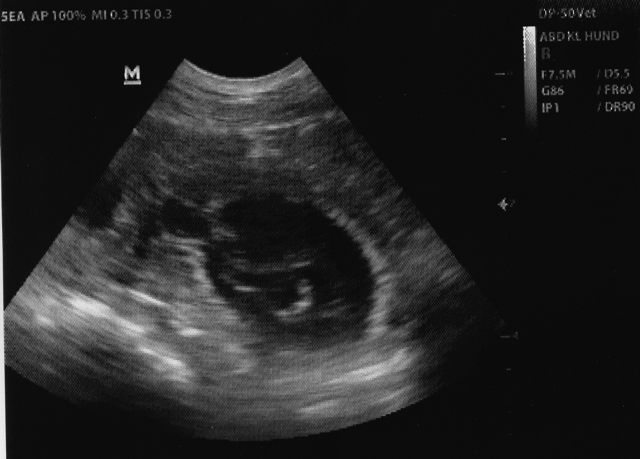

Anfang März erwarten wir Nachwuchs aus der Verpaarung Ynka vom Haus Wirkus und Dante Primus von Erfurther Hof | |

Ynka vom Haus Wirkus, HDF A1, ED 0/0, PRA frei Ausstellungen: 07.07.2013 Dorsten V 2 Reserve Jg-CAC, Reserve VDH Jg-CAC Vater: M-Atze Baikis´Esperanza, HDF A 2, ED 0, AD, BH, Dt.Ch. (VDH), KFT Ausst. -Ch., Dt.Bsg., Mutter: Udet vom Haus Wirkus, HDF A1, ED 0/Gf, BH

Dante Primus von Erfurther Hof, HDF-A 2, ED-0-0, PRA-frei Ch. J. KfT, Dt. Jgd. Ch. VDH, German-Winner 2015, Dt. Ch. VDH, Ausst.-Ch. Kft, Dt. Ch. KfT BH, IPO 2